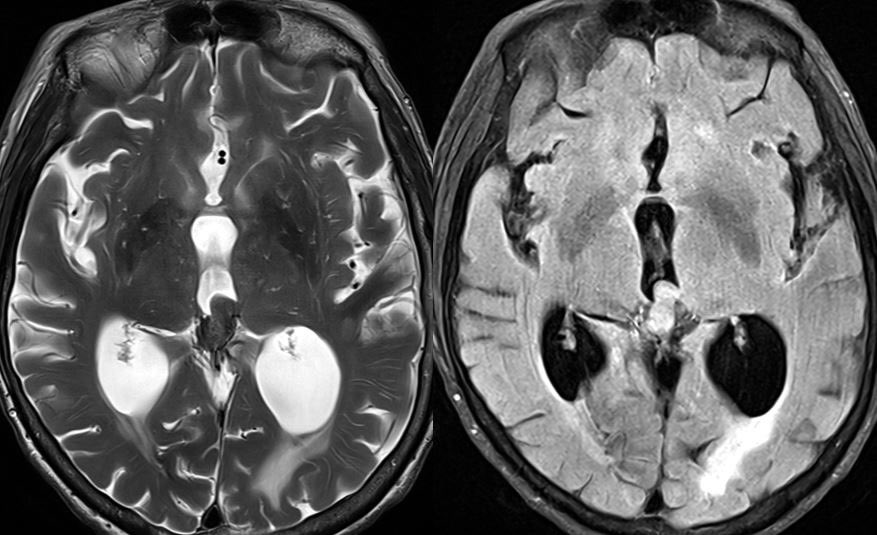

80 y/o patient presenting w/ headache is found to have a pineal mass and hydrocephalus. What is the most likely diagnosis and cause of the hydrocephalus?